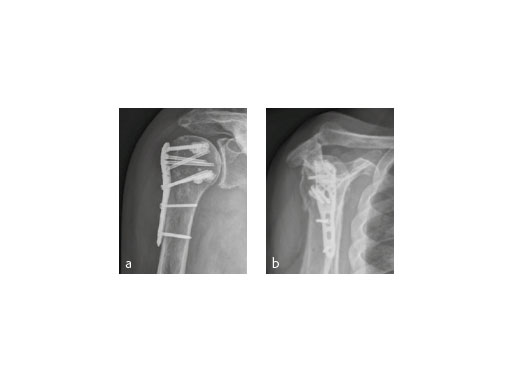

The patient was placed in supine position, having the shoulder on two shoulder supports. After closed reduction of the shoulder, ORIF was performed via an anterior deltopectoral approach using the PHILOS. Four screws were augmented with Traumacem V+ under fluoroscopic control. Initially the treated shoulder was immobilized in a sling for 2 days followed by a pain-adapted functional treatment (Fig 6).

The X-ray review at 3 months after surgery showed an anatomic reduction of the fracture, nicely formatted augmentation, no secondary loss of reduction, and range of motion of the arm reaching the horizontal plane (Fig 7).